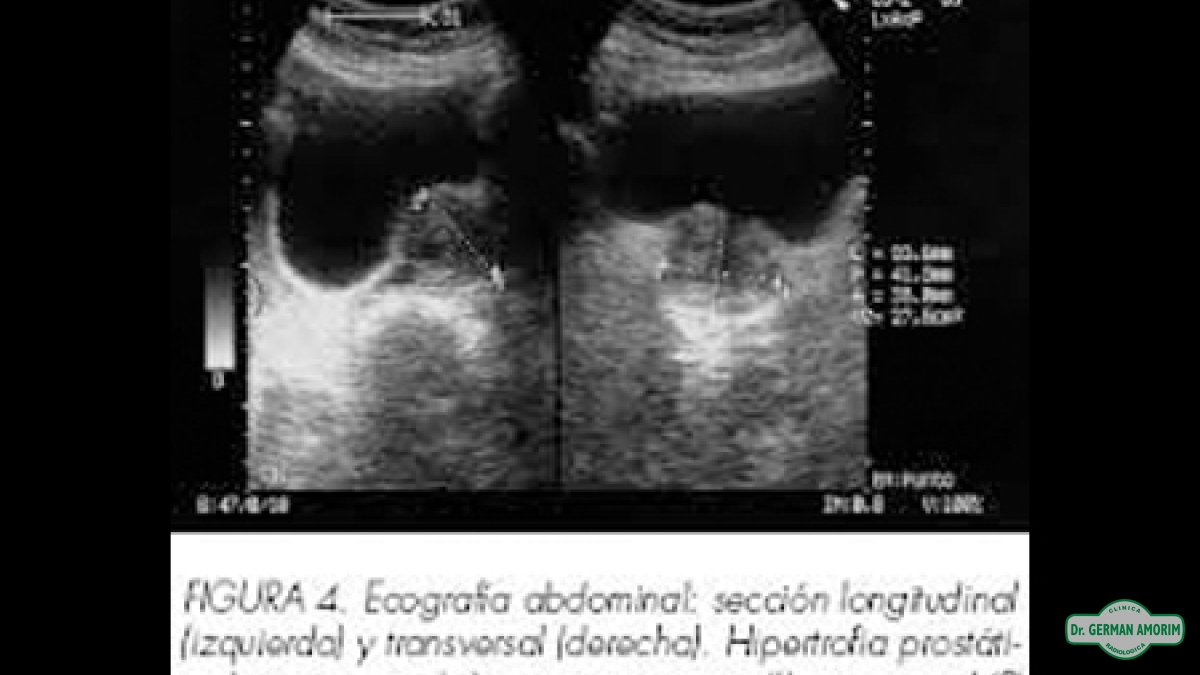

El ultrasonido de la próstata utiliza ondas sonoras para producir imágenes de la glándula prostática.

En este estudio se puede medir sus dimensiones, su peso, visualizar, deformaciones e irregularidad de las paredes.